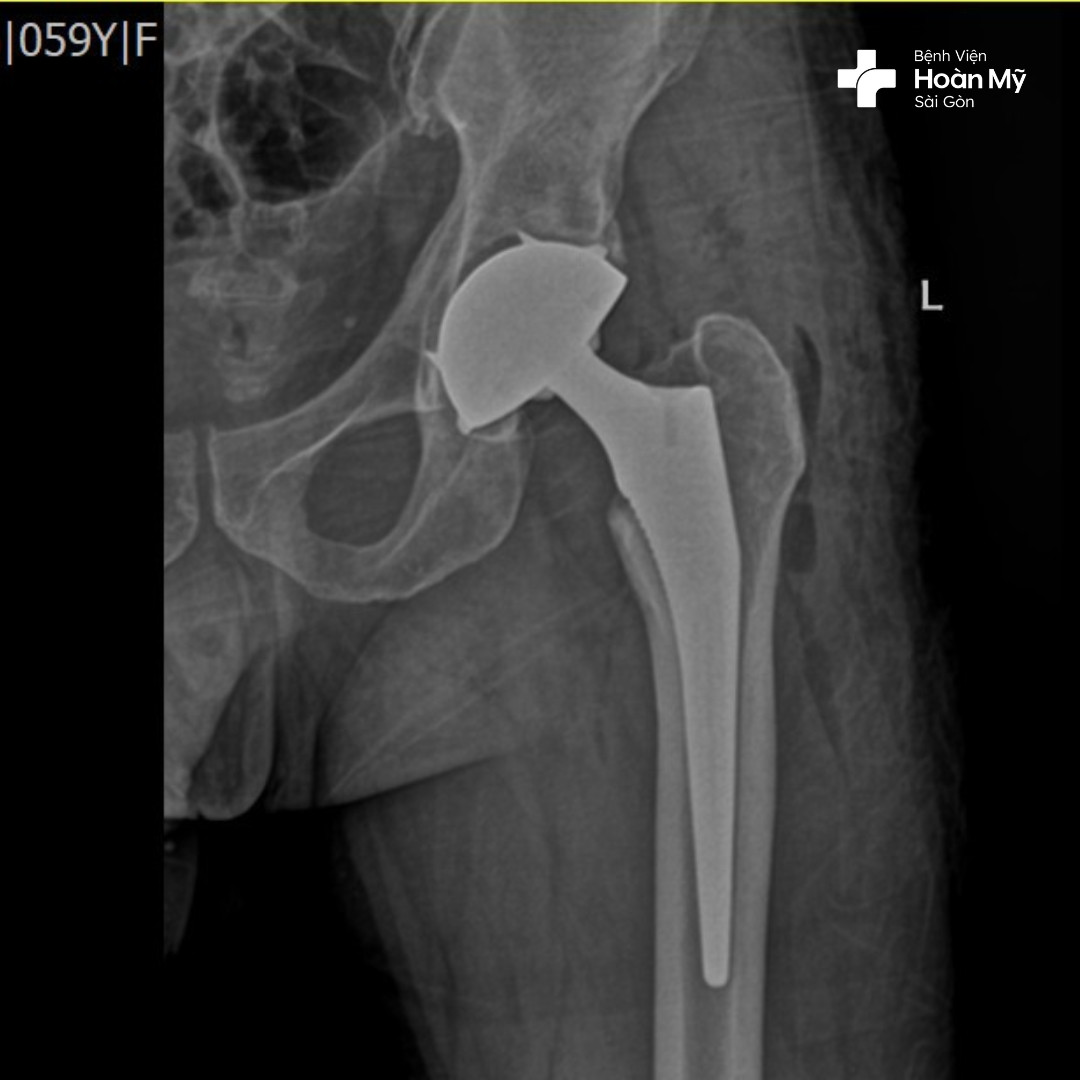

Hình ảnh X-quang sau phẫu thuật thay khớp háng của người bệnh

Thay khớp háng toàn phần

Thay toàn bộ phần mặt khớp của xương đùi và ổ cối. Phẫu thuật này được chỉ định khi bệnh nhân bị các tổn thương khớp như thoái hóa, hoại tử vô khuẩn… và kỹ thuật này có thể thực hiện thay 2 bên cùng lúc giúp bệnh nhân lấy lại chức năng vận động sớm hơn.

Thay khớp háng bán phần:

Chỉ thay thế phần chỏm xương đùi mà không thay thế ổ cối; đây là phẫu thuật được chỉ định các trường hợp chấn thương gãy cổ xương đùi ở người già, hoặc những trường hợp thể trạng yếu không thể đảm bảo thực hiện thay khớp háng toàn phần.

Kỹ thuật tiên tiến này được thể hiện trong quá trình phẫu thuật thay khớp háng, bác sĩ phẫu thuật chỉnh hình tại bệnh viện Hoàn Mỹ Sài Gòn sẽ THAY THẾ cả HAI đầu khớp háng bị hư hỏng bằng các bộ phận nhân tạo cùng một lúc giúp người bệnh không phải chịu đau 2 lần, tránh được biến chứng phẫu thuật, tiết kiệm về tài chính. Đây là kỹ thuật đòi hỏi tay nghề cao của bác sĩ có nhiều năm kinh nghiệm.